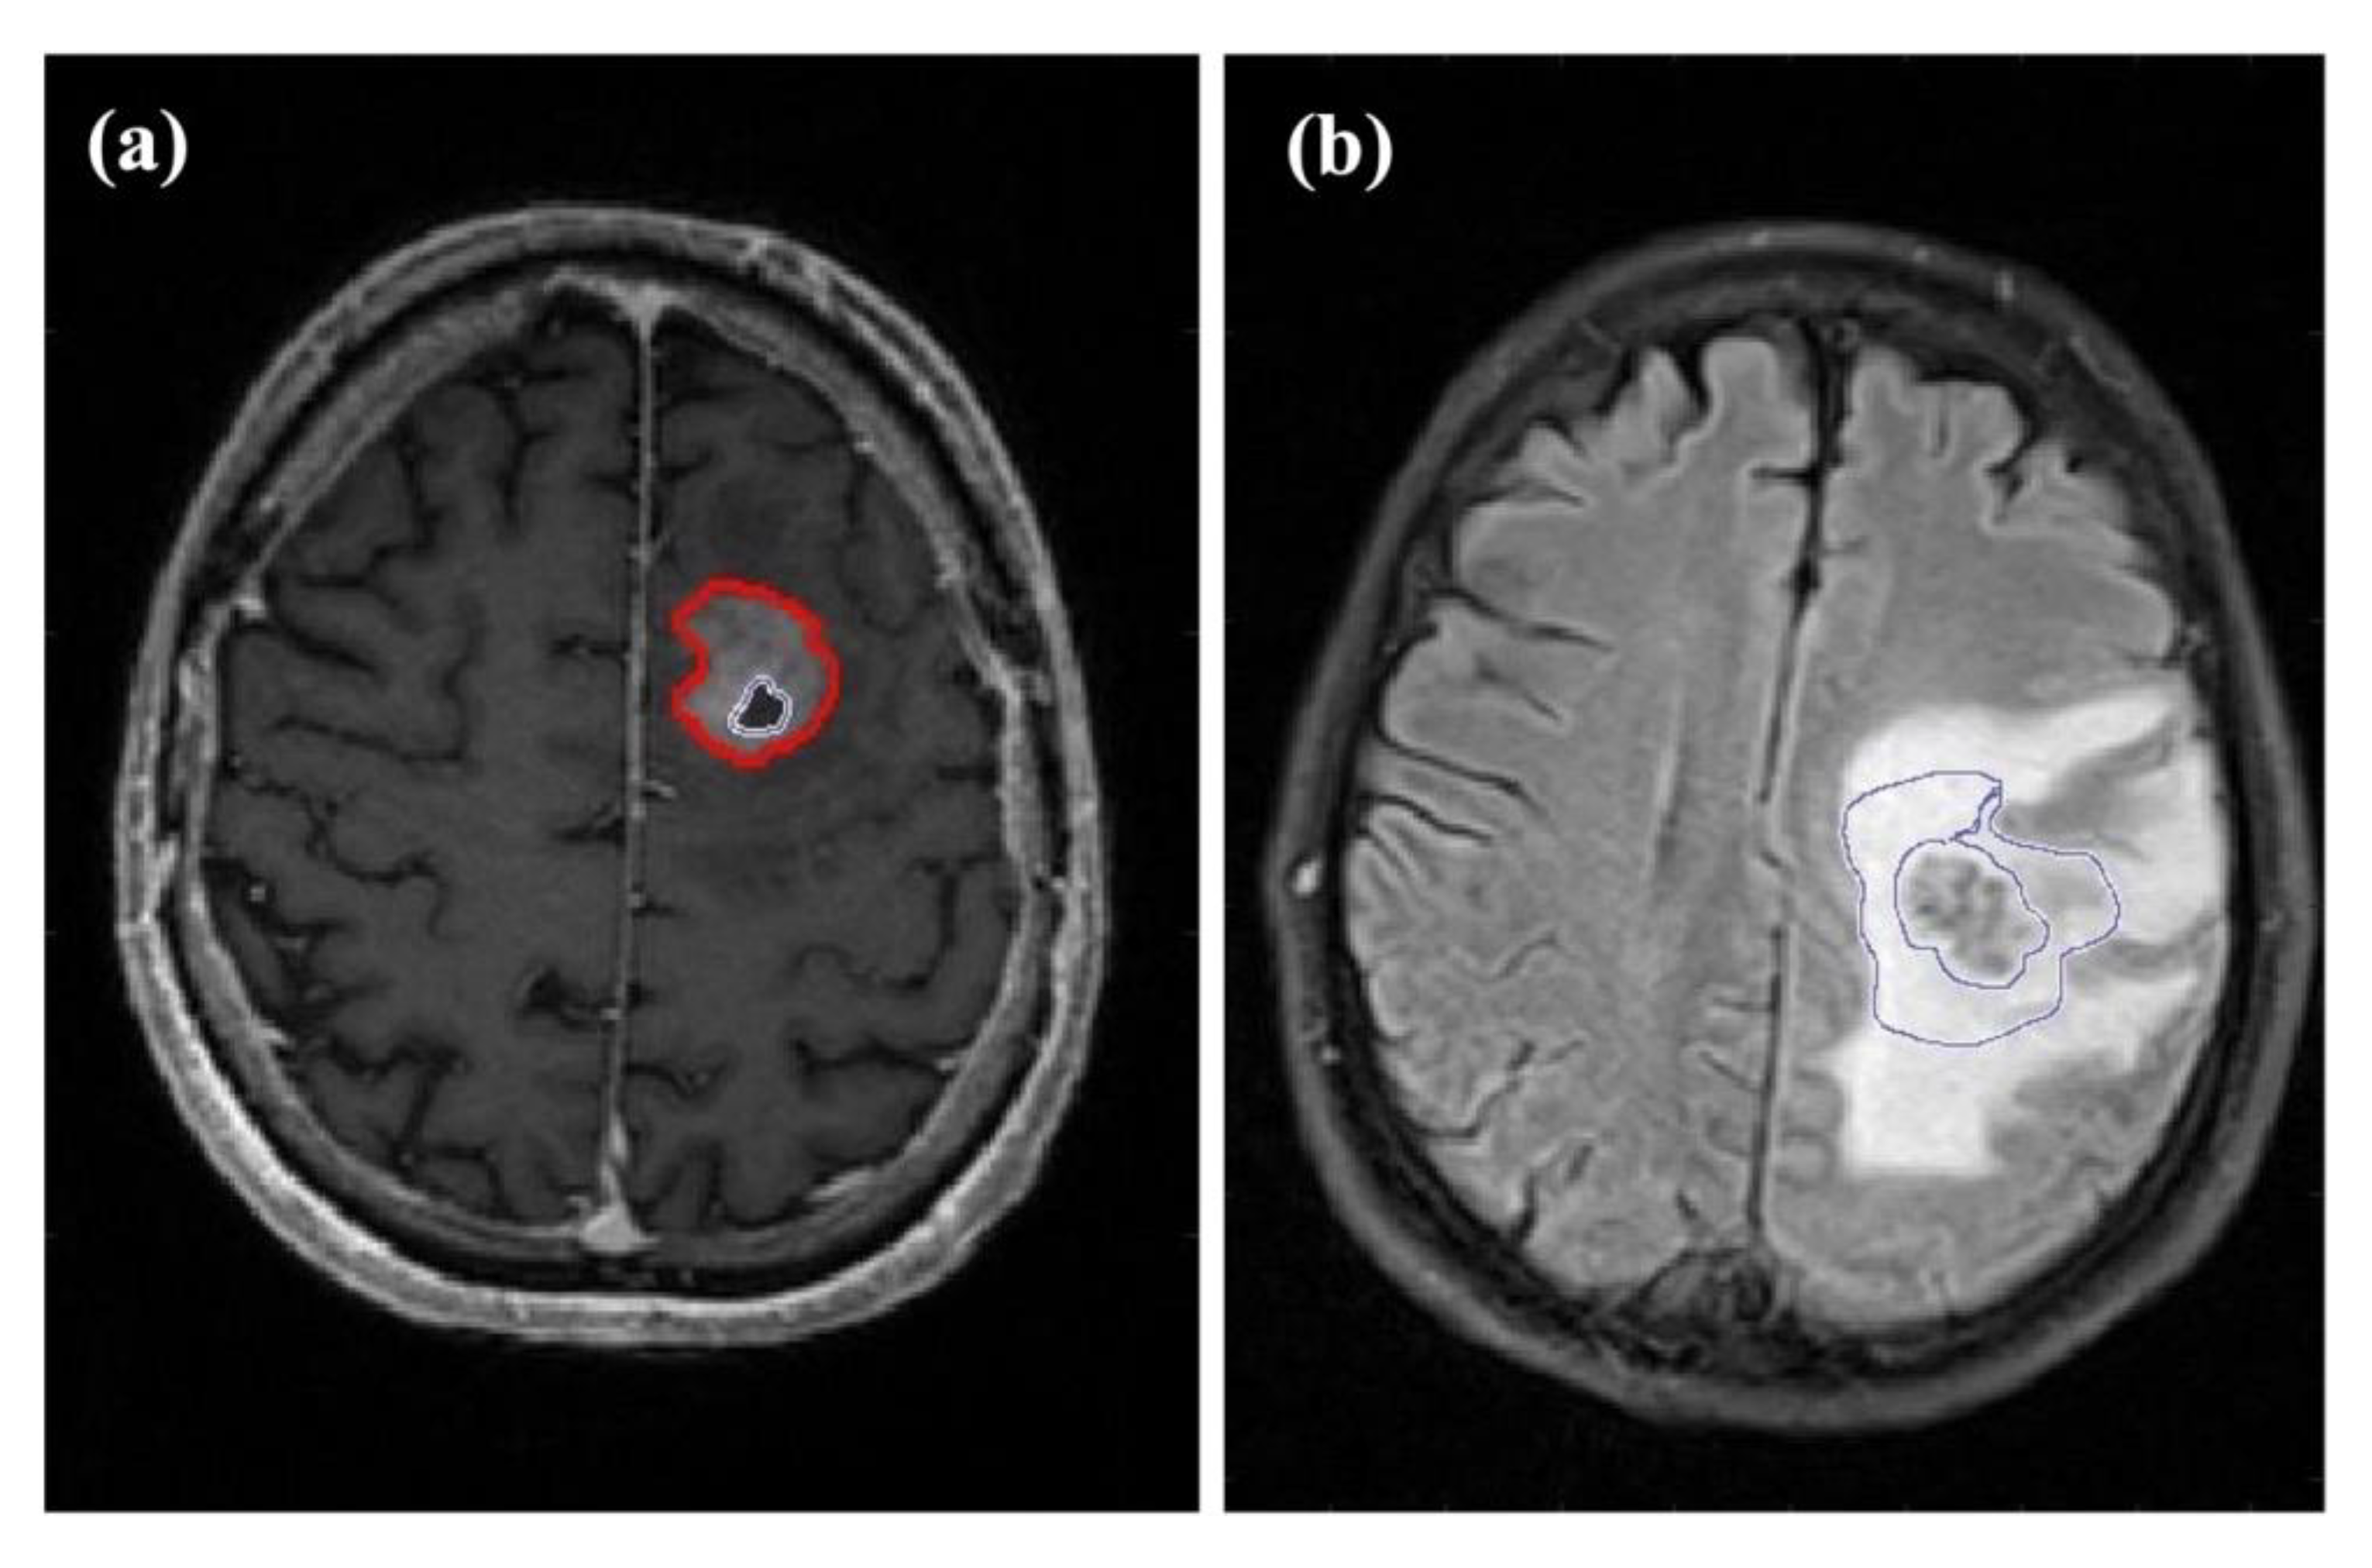

2.3. Image Processing

2.4. Calculation of Perfusion and Oxygenation Parameters

2.5. Artificial Neural Network